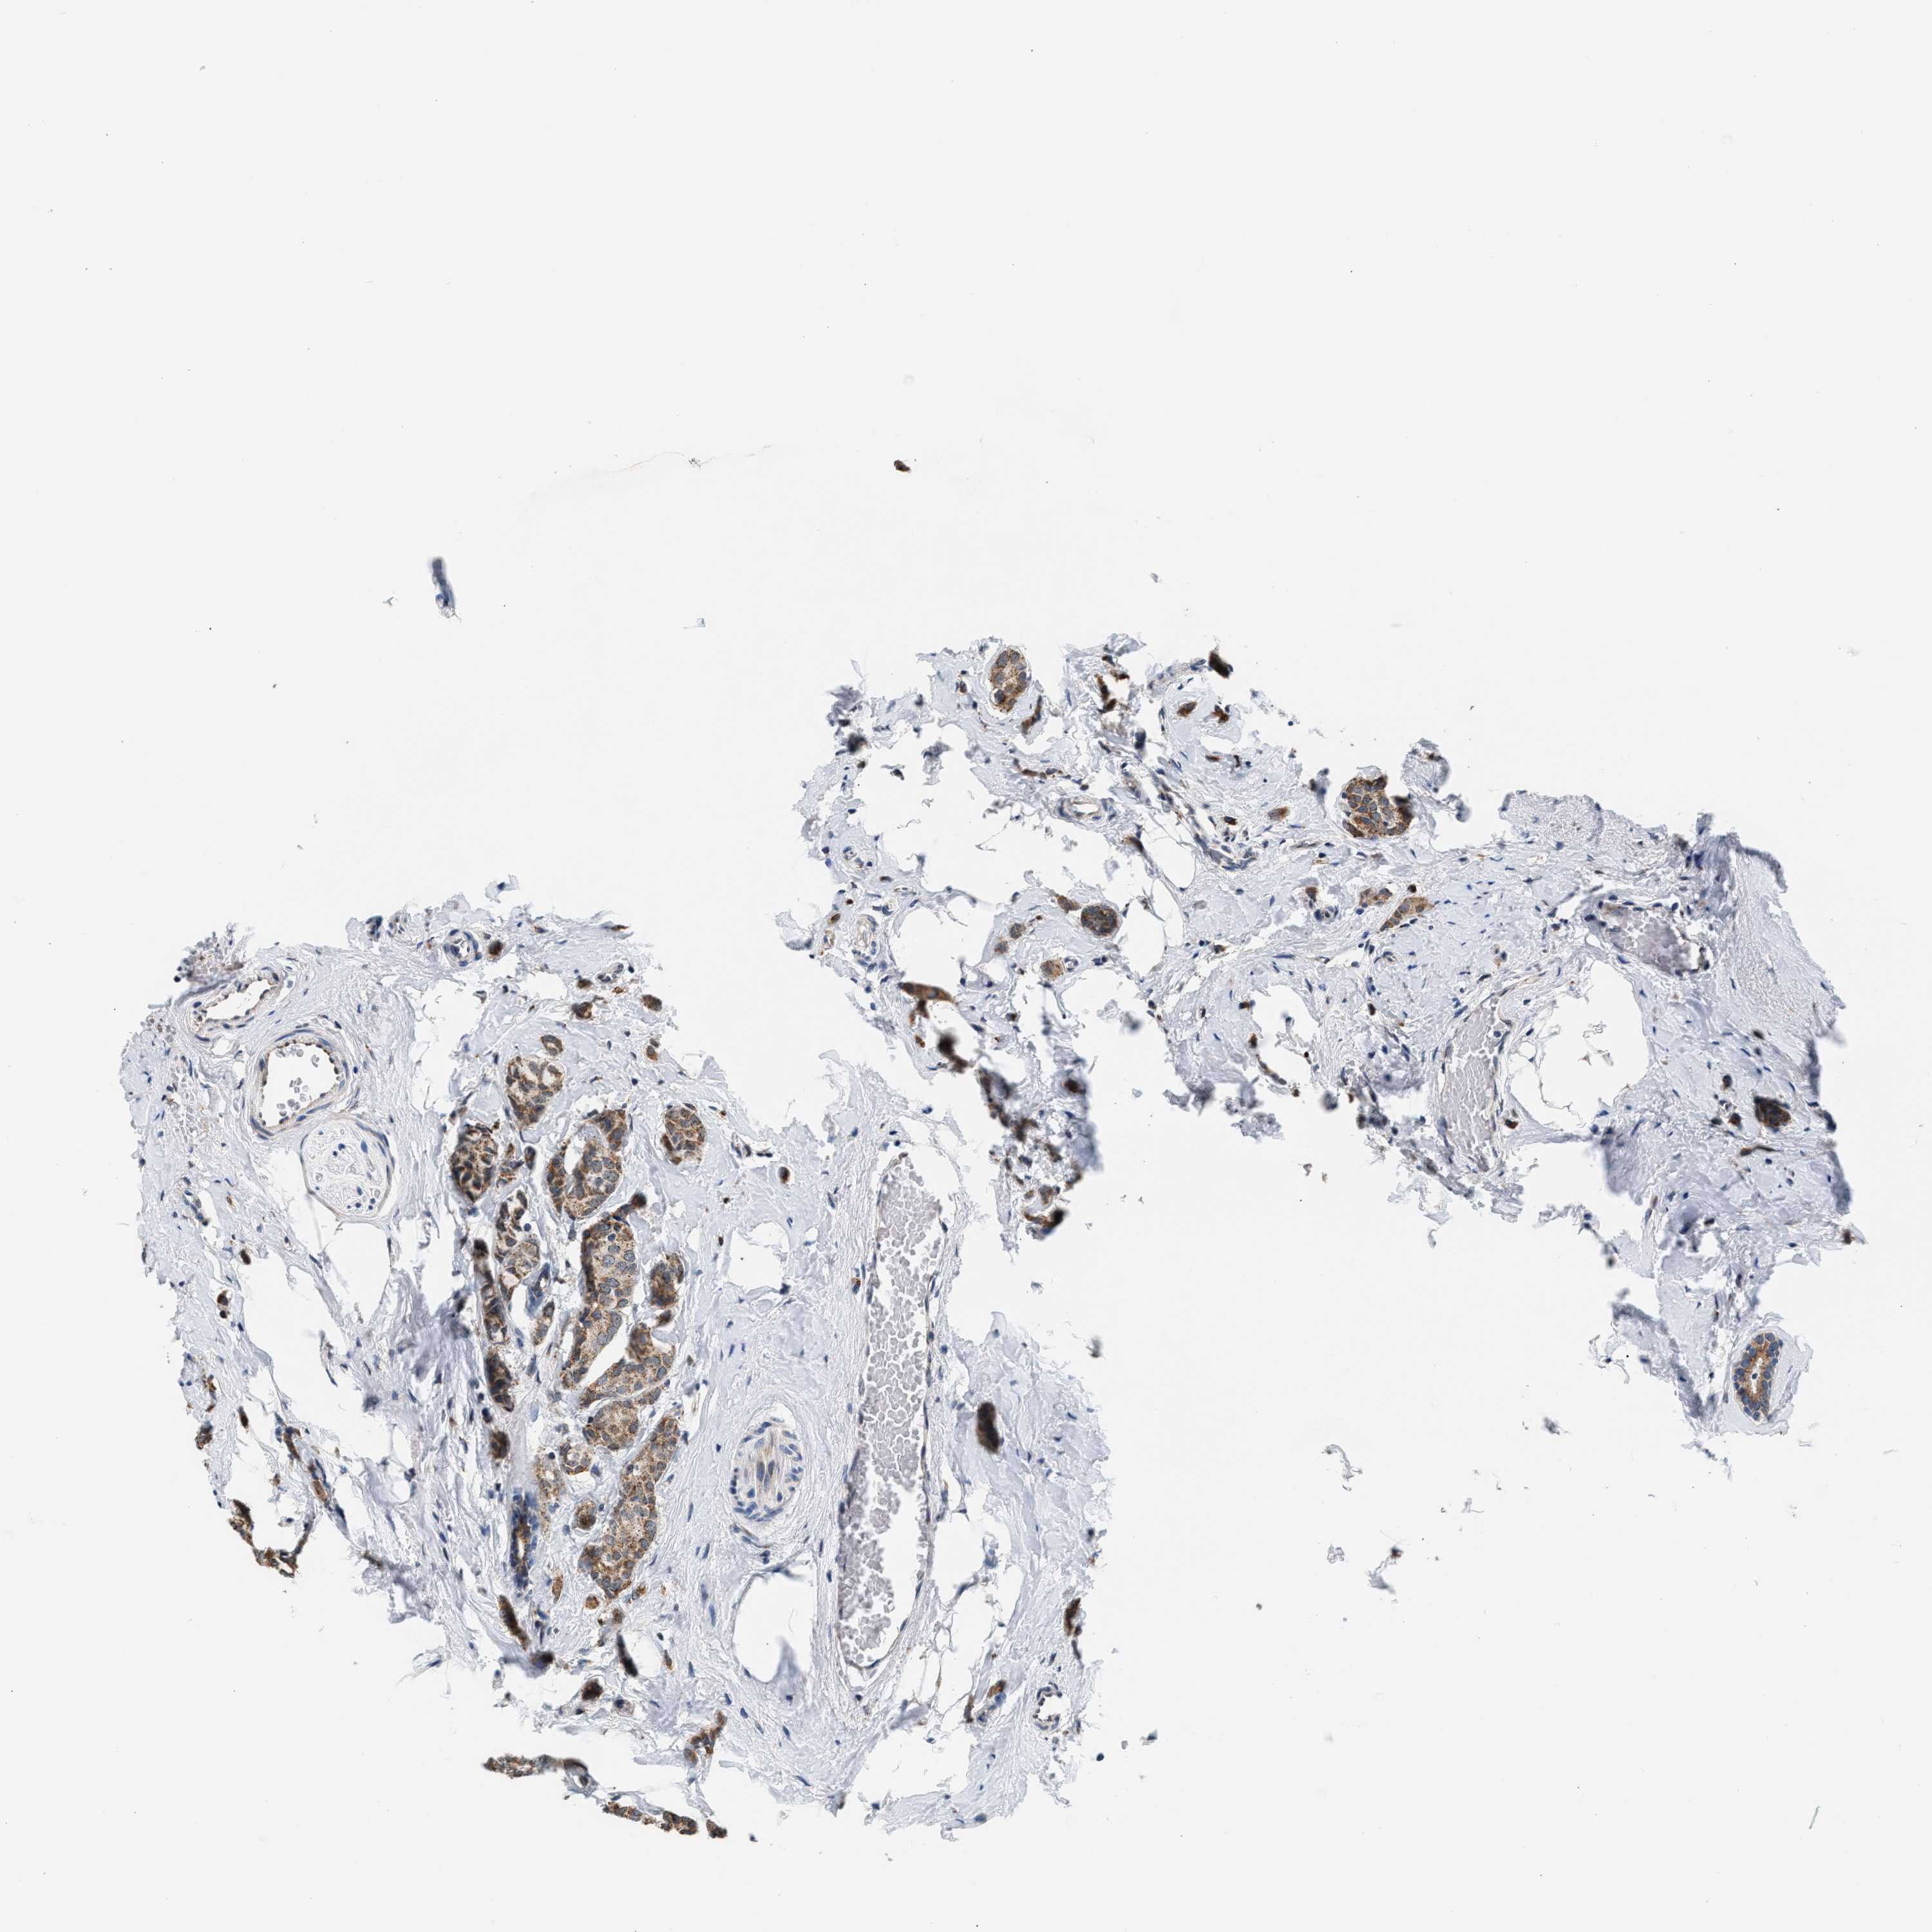

CANCER BREAST CANCER Show tissue menu

BRCA TCGA BRCA VALIDATION PROTEIN EXPRESSION